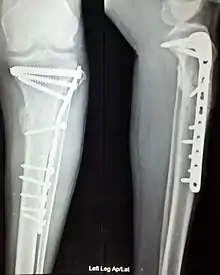

Open Reduction Internal Fixation (ORIF) involves the implementation of implants to guide the healing process of a bone, as well as the open reduction, or setting, of the bone. Open reduction refers to open surgery to set bones, as is necessary for some fractures. Internal fixation refers to fixation of screws and/or plates, intramedullary rods and other devices to enable or facilitate healing. Rigid fixation prevents micro-motion across lines of fracture to enable healing and prevent infection, which happens when implants such as plates (e.g. dynamic compression plate) are used. ORIF techniques often are used in cases involving serious fractures such as comminuted or displaced fractures or, in cases where the bone otherwise would not heal correctly with casting or splinting alone.

Various techniques of minimally invasive surgery for internal fixation of bones have been reported. The treatment of fractures of the distal third of the tibia has evolved with the development of improved imaging and surgical techniques.[5]